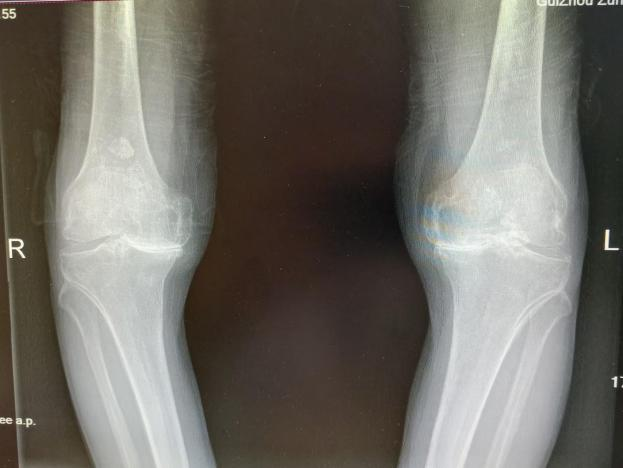

12月17日,贵州航天医院第88次晨读会由我院骨一科主任、副主任医师陈明勇作学术交流,他以“肱骨近端骨折并肩关节脱位的手术治疗”为题,全面讲解了该损伤的手术策略、术中血供保护理念及内侧支撑重建技术等内容,并通过多个典型病例图文资料分享了从损伤机制分析、手术步骤实施到术后随访评估的完整过程与关键细节,为临床处理此类复杂骨折提供了较为全面的技术参考,有助于在手术规划中结合个体情况开展针对性治疗。 贵州航天医院 骨科专家简介 陈明勇 骨一科主任,副主任医师 临床擅长:从事创伤骨科工作约20年,对骨缺损、骨不连、骨肿瘤、肢体畸形等的肢体矫形重建及功能重建,慢性化脓性骨髓炎的根治治疗、糖尿病足的保肢治疗、快速康复理念(ERAS)下的老年骨折的诊治,四肢复杂骨折的诊治,四肢骨折等微创手术治疗具有丰富的临床经验。 2004年毕业于遵义医学院临床专业,曾在中国人民解放军总医院、广西医科大学第一附属医院、上海第六人民医院骨科进修。中国中西医结合学会骨伤科专业委员会横向骨搬移治疗糖尿病足及微血管网再生学组首届委员,遵义市医学会创伤分会常务委员。 瞿 晖 骨科党支部书记,骨二科主任,副主任医师 临床擅长:对骨科的常见病、关节外科、脊柱外科及运动医学疾病的诊治具有丰富的临床经验,熟练掌握骨科手术操作技术。 毕业于遵义医学院临床医学系,2005年前往广州中山大学第一附院骨显微医学部进修学习,2011年前往成都华西医院进修学习,并多次在省内外学习骨科相关知识,是中华医学会骨科分会会员。 赵小锋 中共党员,骨二科副主任,副主任医师 临床擅长:从事骨科临床工作11年,对骨科常见病、多发病诊疗有较为丰富的临床经验,擅长脊柱相关疾病诊断及治疗,尤其是颈、腰、腿疼痛疾病诊断及治疗,擅长胸腰椎骨折微创经皮穿刺内固定术、经皮穿刺椎体成形术、经皮穿刺脊柱内镜下腰椎间盘摘除术、单纯开创腰椎间盘摘除术、腰椎滑脱复位椎间植骨椎融合内固定术、腰椎管狭窄减压融合内固定术及人工髋、膝关节置换术等。 2012年毕业于遵义医学院外科学专业硕士研究生,2019年参加“遵义市115医学人才精英计划”于上海交通大学第一附属医院培训学习,2023年于北京大学第三人民医院脊柱外科进修学习,曾获得遵义市优秀医师荣誉称号。 遵义市手外科第一届委员,遵义市医学会创伤分会第一届委员,遵义市医学会创伤分会第二届委员,贵州省康复医学会第三届脊柱脊髓专业会委员,遵义市医学会烧伤与整形外科学分会委员,发表论文5篇,其中国家级核心期刊1篇,SCI论文1篇,主持市级课题1项并结题,参与市级课题2项。 赵兴东 骨科主任医师 临床擅长:擅长骨科的常见病及各种创伤、四肢骨折创伤修复、骨感染、手足疾病的诊治和手足体表畸形的矫形整复,熟练掌握骨科四肢骨病及创伤的手术操作技术,尤其在四肢关节复杂性损伤、手足外伤、组织缺损创面、难治创面的皮瓣修复方面及平足、高弓足矫形方面及四肢慢性疼痛诊治、康复方面具有丰富的临床经验。 硕士研究生,毕业于遵义医学院临床外科系,2015年前往山东省立医院手足外科进修学习;遵义市医学分会创伤分会第一、二届委员,遵义市手外科医学会第二委届员会常务委员;在省级及省级以上期刊发表文章9篇,参编著作2部,参与主持并完成市级课题1项,参与市级课题2项、省级课题1项。 张艳金 中共党员,骨科副主任医师 临床擅长:从事骨外科工作16年,对复合伤、多发伤的救治、四肢骨干骨折、关节周围骨折、骨肿瘤、骨髓炎等诊治具有丰富的临床经验。 中共党员,硕士研究生,2006年本科毕业于山西医科大学第二临床医学院,2011年研究生毕业于北京军区总医院;在“老年COPD患者合并髋部骨折的诊治”国际合作课题组研究两年,在老年髋部骨折的诊治方面具有丰富的经验,并发表论文6篇;主持遵义市级课题1项,承担遵义医科大学的临床教学工作,获得遵义医科大学优秀带教老师荣誉。编撰有《骨科疾病诊疗精粹》一书,开展2项新技术,编撰地方规范《务川自治县创伤骨科常见疾病诊疗规范》一书。 张俊凯 骨科副主任医师 临床擅长:从事骨科临床工作28年,对创伤骨折、骨感染、骨缺损、骨不连等外科诊治,四肢骨折的微创手术治疗,四肢复杂骨折(如关节内粉碎性骨折、多发骨折等)的损伤控制及手术治疗等具有丰富的临床经验。 1995年毕业于遵义医学院临床专业,2009年前往复旦大学附属医院骨科进修1年。 卢懿明 中共党员,骨科副主任医师 临床擅长:从事骨科工作18年,对创伤骨折、四肢骨折的微创手术治疗、四肢复杂骨折(如关节内粉碎性骨折、多发骨折等)的损伤控制及手术治疗,尤其是髋部骨折的PFNA等微创技术,踝关节骨折、膝关节周围骨折的Mipo微创技术等具有丰富的临床经验,开展了4项新技术,发明6项新型专利技术。 2005年毕业于遵义医学院临床专业,2017年,前往南方医科大学第三附属医院骨科进修半年,回院后运用Mipo技术对骨干骨折及干骺端骨折的治疗技术,同时积极开展骨盆骨折、髋臼骨折腹直肌外侧切口的应用;发表了多篇专业论文,经常参与省内外学术交流会授课,获得医院荣誉称号多个。 邬夏荣 骨科副主任医师 临床擅长:从事骨科工作16年,对四肢复杂骨折、骨肿瘤的诊治,尤其是足踝创伤、慢性踝关节损伤、平足症等诊疗具有丰富的临床经验。 2006年毕业于遵义医科大学临床医学专业,曾在陆军军医大学西南医院进修学习,发表多篇骨科学术论文。 余德怀 中共党员,骨科副主任医师 临床擅长:从事骨科工作10余年,对运动医学、骨关节、脊柱外科常见病、多发病的诊治具有丰富的临床经验。 硕士研究生,2011年毕业于遵义医学院临床医学专业,曾前往遵义医科大学附属医院运动医学专业进修学习;是贵州省医学会运动医学分会青年委员,西部关节镜联盟委员;发表多篇骨科学术论文。 冯 乾 骨科副主任医师 临床擅长:从事骨科工作近20年,熟练掌握骨科多发病及常见病的诊治,尤其对脊柱退变性疾病的诊断及治疗具有丰富的临床经验,主要研究脊柱微创相关治疗方式,能熟练开展椎间孔镜及UBE。 曾前往北京大学第三医院进修学习疼痛及椎间孔镜、首都医科大学友谊医院专业进修脊柱内镜;是贵州省康复医学会第三届脊柱脊髓专业委员会委员;发明专利3项、发表脊柱外科专业论文多篇。 贵州航天医院骨科简介 基本情况 贵州航天医院(原3417医院)骨科组建于1968年,前身是以创伤和断肢(断指)再植闻名于世的上海市第六人民医院骨科,中国断肢(断指)再植的奠基者、中科院院士陈仲伟等专家莅临科室指导医疗和教学,并在70年代开展了贵州省首例断肢(断指)再植手术。组建50余年来,诊治患者已逾百万,挽救了无数的伤病员,成为了保障遵义地区人民群众健康的重要支撑。 经过几代人的不懈努力,今天的骨科,已由创伤骨科发展至骨病、骨肿瘤、骨结核等领域,现有脊柱外科、关节外科、四肢创伤、手足外科四个亚专科,成为了集医疗、教学、科研于一体的综合学科,是贵州省临床重点专科、遵义市临床重点专科、遵义市骨科临床医学中心、遵义市基层骨科专科联盟理事长单位。 科室目前开放床位110张,共有医护人员50余人,副高级以上专家18人,硕士研究生15人。拥有一流骨科医疗设备多台,每年不定期选派优秀技术骨干到全国各大知名医学院校进修、学习、参观、交流,并邀请国内、国外知名专家教授来院进行交流、指导,通过不断引进国内外先进的诊疗技术,科室医疗技术水平稳步提升,为广大人民群众提供了优质的医疗服务。 专科特色 骨一科 (一)骨缺损、骨不连的肢体与功能重建 胫骨横向骨搬移技术治疗糖尿病足: (二)慢性骨髓炎的根治治疗 (三)肢体缺血性疾病如糖尿病足、脉管炎的保肢治疗 (四)皮瓣修复 (五)复杂创伤的治疗 (六)老年髋部骨折及小儿骨折快速手术 老年髋部骨折: 骨二科 (一)胸腰椎骨折微创经皮椎弓根螺钉固定术 (二)老年性骨质疏松性患者腰椎滑脱脊柱内固定术(骨水泥螺钉) (三)V形双通道脊柱内镜技术(VBE)腰椎融合术治疗腰椎退行性疾病 (四)老年性骨质疏松性骨折(PVP/PKP)术 (五)人工髋关节置换术 (六)双侧股骨头坏死人工全髋关节置换 (七)右侧全髋置换术后假体周围骨折翻修 (八)人工膝关节置换术 (九)人工膝关节假体松动翻修 (十)关节镜技术 传统手术切口 关节镜技术切口 诊疗范围 骨一科 1.四肢创伤、矫形。 2.手、足踝外科。 骨二科 end